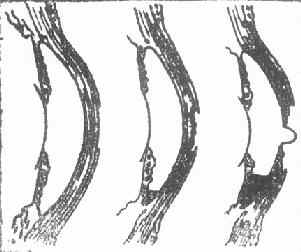

角膜溃疡

1、上皮脱落  2.溃疡及前房积脓 3.后弹力层膨出

图6-1 角膜溃疡

角膜溃疡进行性演变

图6-2 角膜溃疡进行性演变

(三)恢复期即炎症的转归阶段。经过治疗,溃疡可逐渐转向清洁,周围健康角膜上皮细胞迅速生长,将溃疡面完全覆盖,在角膜上皮细胞的掩盖下,角膜基质的成纤维细胞增生和合成的新胶原,修补基质的缺损处,角膜溃疡遂告痊愈。角膜中央区溃疡愈合方式多为无新生血管性愈合;周边部溃疡多为有血管愈合。新形成的角膜基质胶原纤维排列紊乱,构成了不透明的瘢痕组织。位于中央区的致密瘢痕可使患眼视力严重丧失。浅层溃疡,仅有角膜上皮层覆盖创面,无结缔组织增生者,则在损伤处形成透明的小凹面,荧光素不染色,称为角膜小面(corneal facet)。(图6-1,6-2)